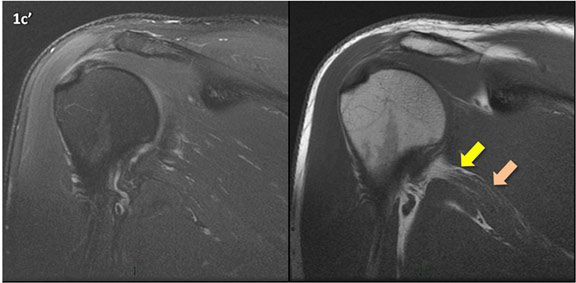

Figura 1 (a-g): Imagens consecutivas de RM no plano coronal nas ponderações DP com supressão de gordura (DP SG) à esquerda e T1 à direita. Clique na seta para passar as imagens.

Figura 1 (a-g)': Imagens consecutivas de RM no plano coronal nas ponderações DP com supressão de gordura (DP SG) à esquerda e T1 à direita mostrando . Clique na seta para passar as imagens.

Figuras 1b’ a 1g’ mostrando atrofia da porção superior do músculo redondo menor (seta salmão), com lipossubstituição mais evidente das mais fibras laterais (seta amarela). As fibras mais inferiores e mediais têm atrofia menos evidente.

Repare que estas alterações não são evidentes nas imagens com supressão de gordura.